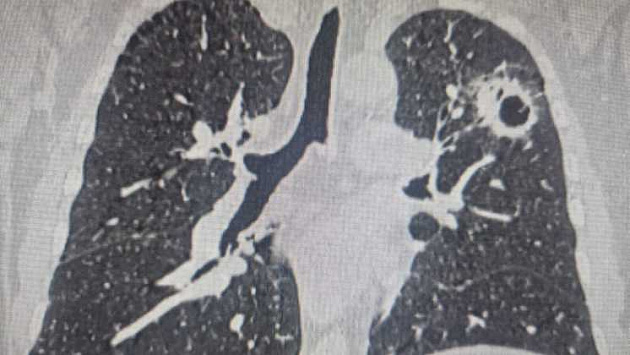

Сначала у пациента обнаружили центральный рак правого легкого. Вместо стандартного удаления всего легкого хирурги провели органосохраняющую операцию, что позволило сохранить две трети правого легкого.

Через год у мужчины выявили вторую опухоль - уже в левом легком. Причем между этими операциями пациенту удалили щитовидную железу, где также обнаружили рак.